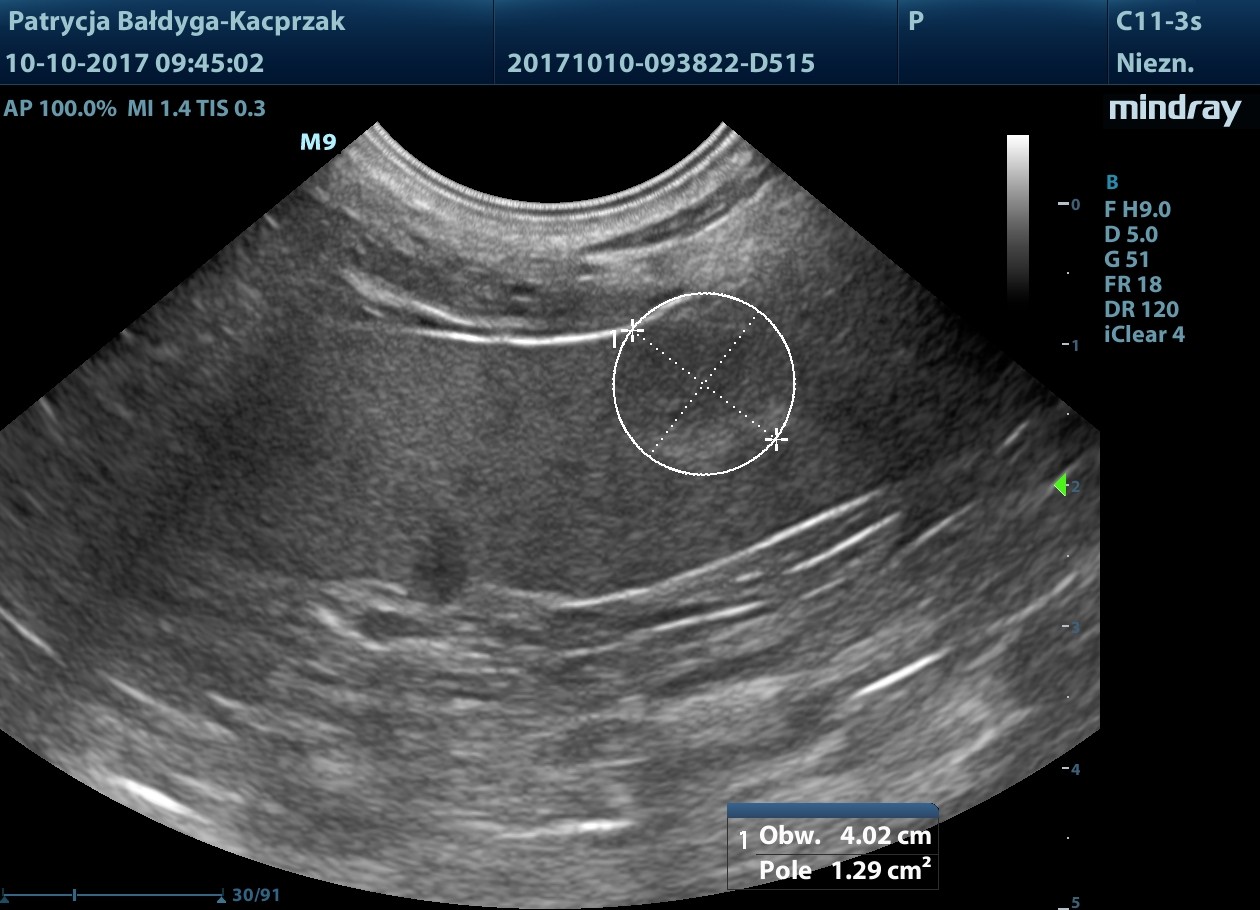

w końcowym odc. okręznicy poprzecznej nadśledzionowo widoczna zmiana ogniskowa

naciekowa, śródścienna, hipoechogenna, niesymetryczna 6-18 mm, dł. 2,5 cm, warstwowość w tym miejscu zatarta, obecny okoliczny, nieznaczny odczyn zapalny (pod koniec filmu 3), ww, chłonne okrężnicze środkowe reaktywne, powiększone, hipoechogenne, zokrąglone, śr. ok. 7-8 mm